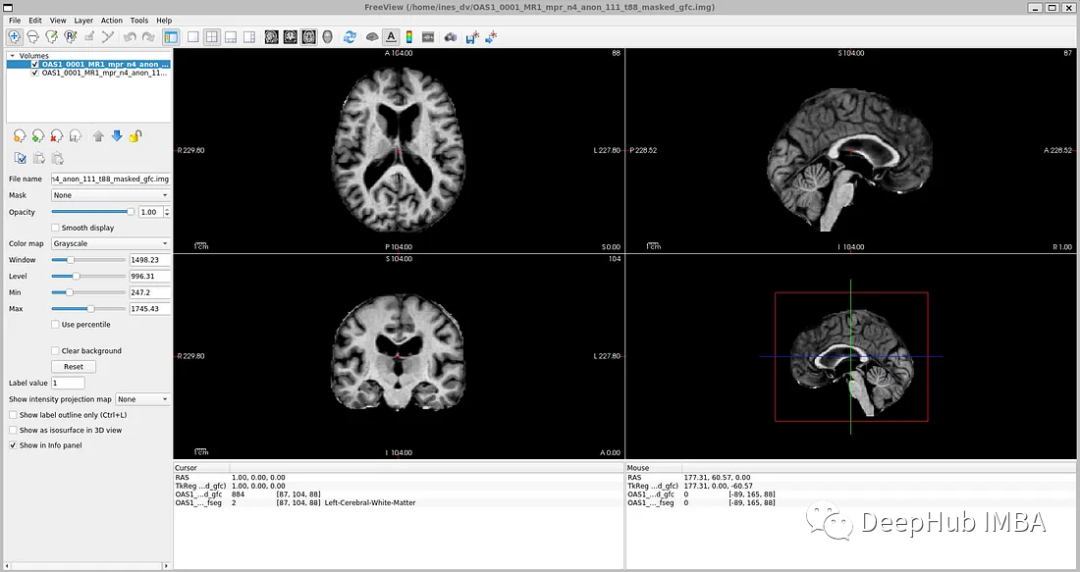

如果你打开' oasis_crosssectional_disc1 .tar.gz ',你会发现每个主题都有不同的文件夹。例如,对于主题OAS1_0001_MR1,是这样的:

镜像数据文件路径:disc1\OAS1_0001_MR1\PROCESSED\MPRAGE\T88_111\ oas1_0001_mr1_mpr_n4_anon_111_t88_masked_ggc .img

标签文件:disc1\OAS1_0001_MR1\FSL_SEG\OAS1_0001_MR1_mpr_n4_anon_111_t88_masked_gfc_fseg.img

为了可视化带有相应标签的图像,可以使用TorchIO,这是一个Python库,用于深度学习中多维医学图像的加载、预处理、增强和采样。

image_filename = root_dir + '/Oasis_Data_Processed/OAS1_0001_MR1_mpr_n4_anon_111_t88_masked_gfc.nii'

label_filename = root_dir + '/Oasis_Labels_Processed/OAS1_0001_MR1_mpr_n4_anon_111_t88_masked_gfc_fseg.nii'

subject = torchio.Subject(image=torchio.ScalarImage(image_filename), label=torchio.LabelMap(label_filename))

subject.plot()